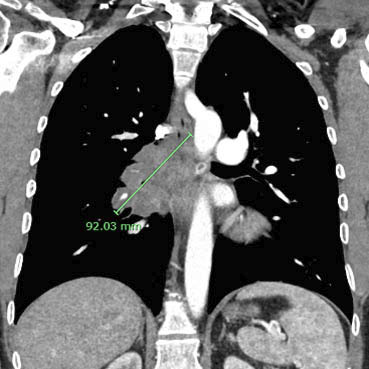

On December 30th I was diagnosed with a stage four malignant melanoma (skin cancer) in my right lung following several rounds of xrays, CT scans and biopsies to determine the root cause of a persistent cough I'd developed several weeks earlier. Based on the diagnosis I recently started an immunotherapy treatment, in which I receive a combination of drugs (administered via IV) that are designed to train my immune system to attack the cancer. For now I'm scheduled to receive the treatments once a month as the doctors monitor how the tumor responds. My oncologist has been very positive about my outlook and I'm very thankful to be living in a time when many relatively new technological and pharmaceutical cancer treatment options are available.